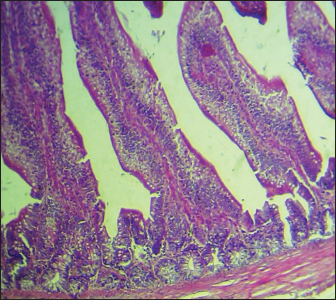

Histopathological study

The results noted in Figures 15 showed that chicks infected with S. enteritidis had edema among the muscular layer with atrophy of some intestinal villi. On the other hand, broilers infected with S. enteritidis and treated with C. myxa showed degeneration of intestinal glands with extensive inflammatory cell infiltration also mild sub-muscular edema, while with curcumin-treated group showed normal intestinal villi architectures, with hyperplasia of intestinal associated lymphoid tissue. The result noted a clear improvement in broilers that received C. myxa and curcumin showing normal intestinal villi with an increase in the number of goblet cells. The data of the present study confirmed the effectiveness of C. myxa and curcumin and especially the synergistic action between them in inhibiting the growth of S. enteritidis bacteria in poultry chickens, improving antioxidants and reducing free radicals, in addition to its action as a good anti-inflammatory at the blood level and suppressing the levels of cytokines that encourage inflammation and its role in improving intestinal tissues and making them close or similar to the health of broiler.

Fig. 1. Cross section of the intestine of poultry refers to normal histological architectures 100×. (H & E).

Fig. 5. Cross section of the intestine of poultry chicks infected with S. enteritidis and treated with C. myxa and curcumin showing normal intestinal villi with an increase in the numbers of the goblet cells (H&E stains, 100×).